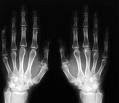

Els rajos X són una radiació de la mateixa naturalea que les ones de radio, les microones, els rajos infrarogos, la llum visible, els rajos ultraviolats i els rajos gamma. Els rajòs X surten de fenòmens extranuclears, a nivell d`òrbita electrònica, fonamentalmet produits per la desacel.leració dels electrons. Aquestos són una radiació ionitzant doncs interactuen amb la matèria produint la ionizació dels átoms de la mateixa . El descubriment d

e Roentgen va consistir en disenyar un aparell que permitira per mitga de una corrent elèctrica produir els RX e impresionar una placa fotogràfica. El 22 de desembre de 1895 va realizar la primera prova amb la mà de la seva dona i va obtindre la primera radiografia de la història. Aquest va ser el comensament de la Radiología que és la branca de la medicina que s` ocupa del diagnòstic per mitga de les imatgens. A partir d`eixos primers aparells de radioscòpia s` han produit motls avancos encara que la base continua siguent la mateixa. Quan els Rx travesen un teixit, una part d`ells queda atrapada en aquest i no impresiona a la placa fotogràfica que posem darrere, així doncs observem la silueta de l`os impresionada a la placa.